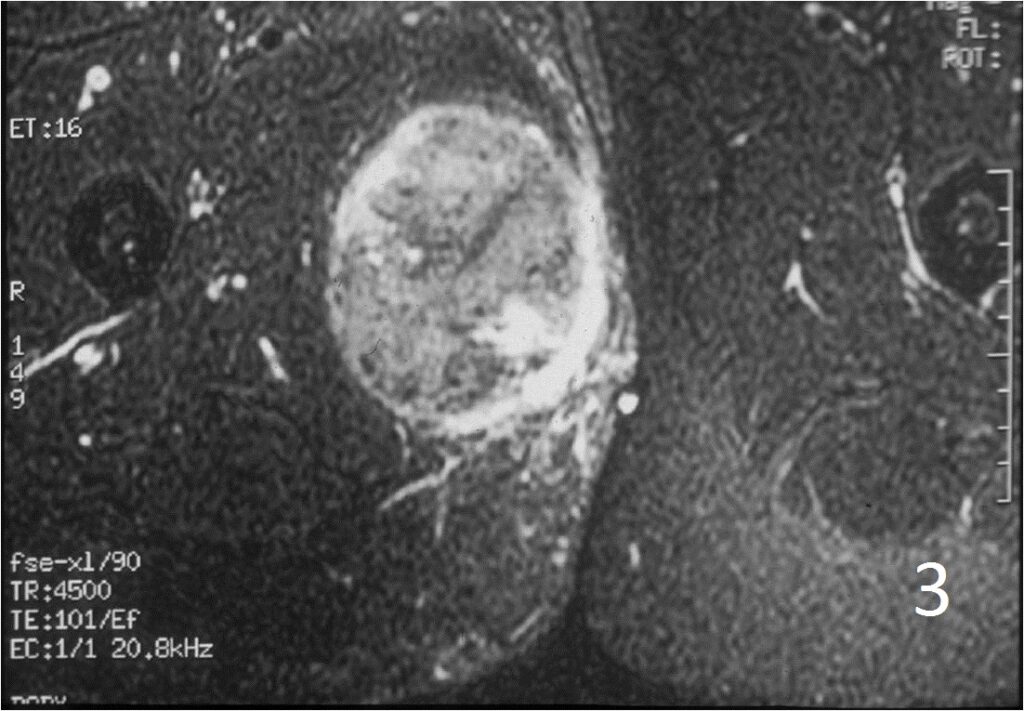

• 60% of fibrosarcomas are intramuscular (Fig. 2, 3, 5, 6, 7, 8)

• Well defined heterogenous mass on T2W (Fig. 4, 9)

Fig. 2-4: An MRI of the thigh shows a mass in the medial compartment that is isointense to muscle on T1W images (Fig. 2) and heterogeneous on T2W (Fig. 3). Sagittal T1W post contrast with gadolinium demonstrates enhancement of the tumor (Fig. 4).